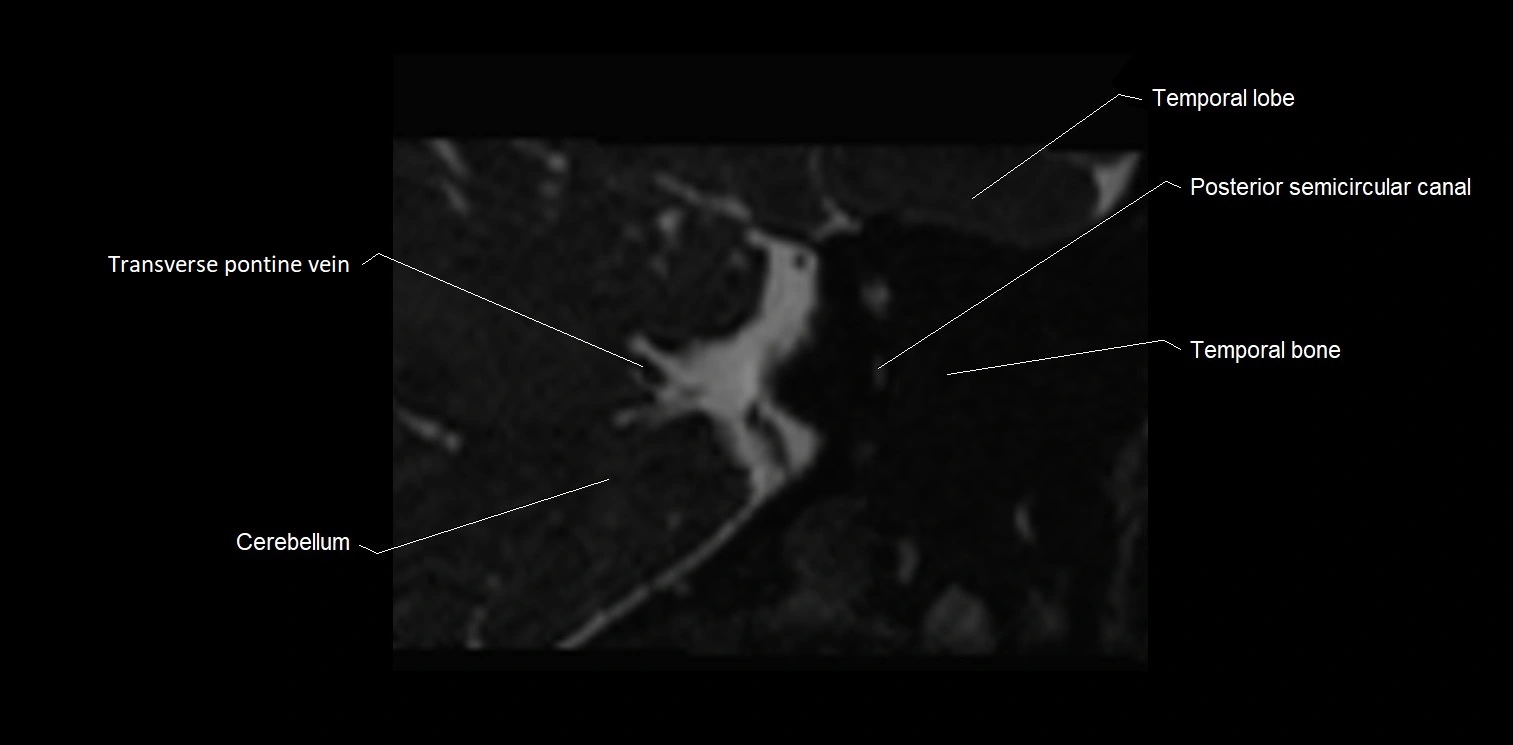

MRI Appearance

• The abducens nerve is a small, thin, linear structure

• Best visualized on high-resolution T2-weighted 3D MRI sequences (e.g., FIESTA or CISS)

• Seen as a hypointense (dark) line running from the brainstem at the pontomedullary junction, traversing the prepontine cistern, and entering Dorello’s canal under the petrosphenoidal ligament, then into the cavernous sinus, and finally the orbit

• May be challenging to visualize in standard MRI due to its small size

• Pathology may be inferred by absence, displacement, or enhancement of the nerve

MRI images

image